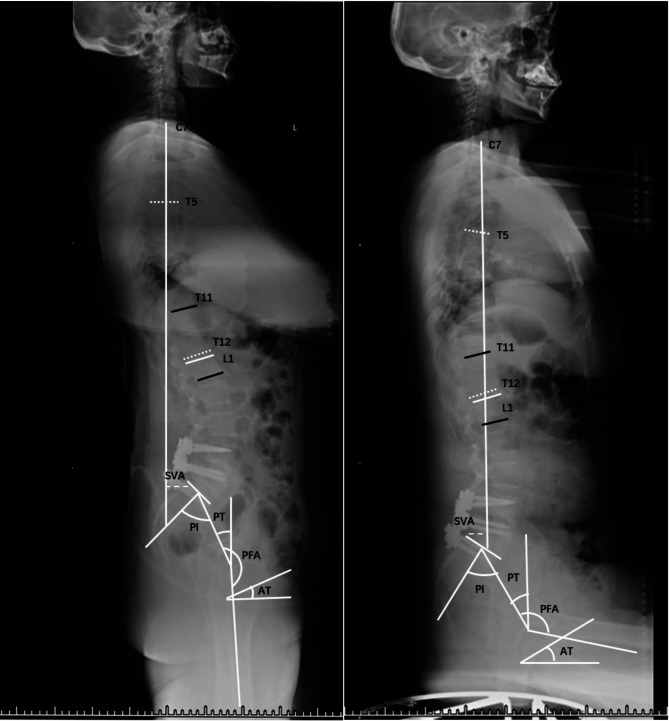

Methods: This cross-sectional study analyzed patients who underwent long- or short-segment instrumented fusion to the pelvis for lumbar degenerative disease at our hospital from June 2018 to October 2019. Patients were grouped based on the number of internal fixation segments, both short and long. Sagittal parameters were measured in standing and sitting positions and matched for sex, gender, height, weight, and other related parameters. Statistical analysis was performed using t-tests and Mann-Whitney U tests.

Results: A total of 98 patients were included, of whom 55 were included in the long-segmengroup (31 men, 24 women; mean age of 63.1 ± 8.5 years). In the long-segment group, no significant changes were observed between standing and sitting positions (P > 0.05). In the short-segment group, significant changes were observed in the sacral vertical axis, pelvic tilt, sacral slope, thoracic kyphosis, lumbar lordosis, T1 pelvic angle, T1 spinopelvic inclination, acetabular tilt, and pelvic-femoral angle between the two positions (P < 0.05). The difference in pelvic femoral angle changes between the groups was also significant (P < 0.05).

Conclusions: In the short-segment group, transitioning from standing to sitting leads to greater sagittal changes, including decreased lumbar lordosis and forward trunk lean, with smaller hip joints than in the long-segment internal fixation group.